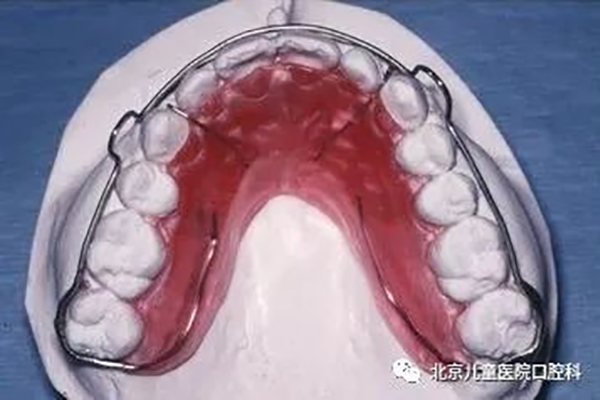

1、Hawley保持器:矫治结束后有利于深咬合的控制,并允许后牙少量调整达到更紧密的咬合关系。

2、环绕式保持器:此类保持器主要用于防止间隙复发。

3、透明保持器:也称压膜保持器,因其透明美观及舒适度高,很多患者选择此类保持器。6-9个月后,常因损坏及染色而需要更换。

多为粘接于牙齿舌面的舌侧丝保持器。常用于下切牙拥挤解除后需要永久保持的成年患者。